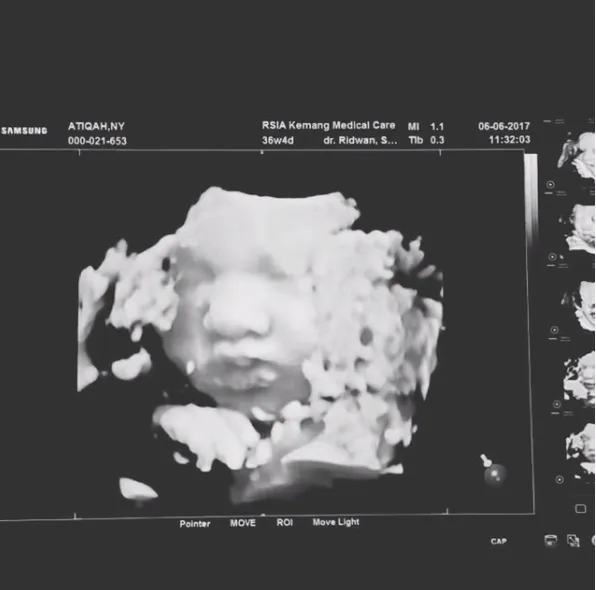

USG Jelang Kelahiran, Wajah Bayi Atiqah dan Rio Nampak Jelas

Tepat di pekan 36, Atiqah dan Rio Dewanto periksa ke dokter dan mereka mendapatkan hasil USG terbaru. Pada video USG kali ini wajah bayi yang ada di dalam kandungan Atiqah nampak jelas.

Pipi bayi itu tembem dan hidungnya pun sudah mancung. Beberapa netizen menyebut bahwa wajah bayi ini sangat mirip dengan Atiqah, meski baru dari hasil USG saja.